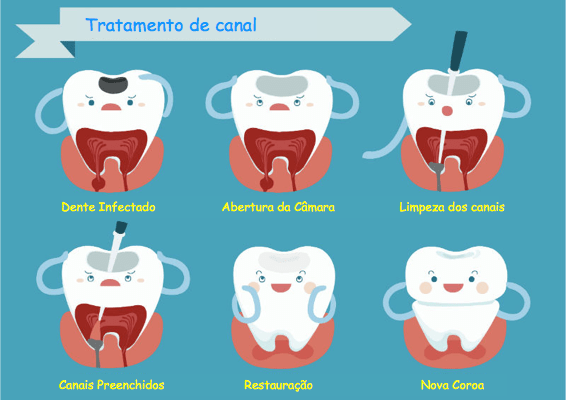

Como Se Faz Canal no Dente: Passo a Passo com Fotos

Você quer ver como é o procedimento? A gente te mostra! O tratamento endodôntico, popularmente conhecido como canal, é um processo detalhado para salvar um dente que sofreu danos severos na polpa, aquela parte interna onde ficam os nervos e vasos sanguíneos.

A Descoberta da Causa Raiz: Tudo começa com uma investigação minuciosa. O dentista usa radiografias para identificar a extensão do problema, como cáries profundas, fraturas ou traumas que levaram à inflamação ou infecção da polpa. É o primeiro passo para planejar a intervenção.

Limpeza e Modelagem Interna: Com o dente anestesiado, o profissional acessa a câmara pulpar. Ferramentas finíssimas, as limas endodônticas, entram em ação para remover todo o tecido inflamado ou infectado. Elas também ajudam a alargar e modelar os canais radiculares, preparando o terreno para a desinfecção.

Desinfecção Profunda: A higiene interna é crucial. Soluções irrigadoras, como o hipoclorito de sódio, são usadas para lavar e desinfetar os canais, eliminando bactérias e garantindo um ambiente limpo. Esse passo é um dos mais importantes para o sucesso do tratamento.

O Selamento Perfeito: Após a limpeza minuciosa, os canais são preenchidos com um material biocompatível, geralmente a guta-percha. Ela é cimentada para vedar completamente o espaço, impedindo a reentrada de microrganismos. É o fechamento do ciclo de limpeza e proteção.

Restauração Final: Por último, o dente recebe uma restauração. Pode ser uma resina composta, um pino ou até uma coroa protética, dependendo do dano. O objetivo é devolver a força e a estética ao dente tratado.